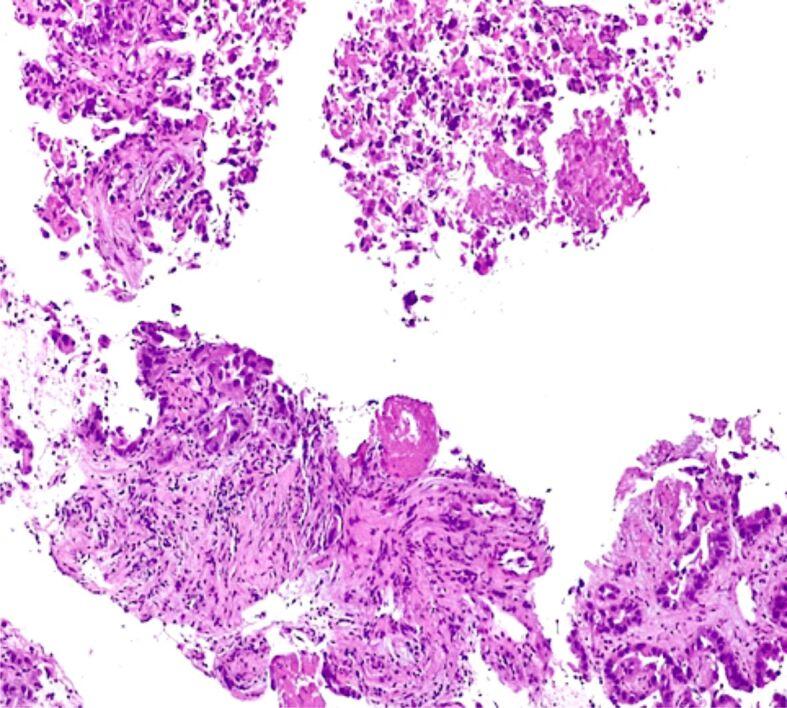

PATIENTS, MATERIALS AND METHODS: Inclusion criterion for this prospective study was identifying patients with pancreatic solid tumors, by means of imaging methods, from January 2018 to February 2020, within the Department of Gastroenterology, Emergency Clinical Hospital, Bucharest, Romania. All patients underwent EUS-FNB and the harvested tissue was sent to the Department of Pathology for histopathological (HP) diagnosis and IHC assessment if tumoral origin remained undetermined.

A total of 57 patients were ultimately selected to take part in our study. We performed immunohistochemical analysis based on the morphological diagnosis of the pancreatic tumors and assessed cytokeratin (CK)7, CK20, caudal type homeobox 2 (CDX2), MutL homolog 1 (MLH1), MutS homolog (MSH)2, MSH6, postmeiotic segregation 2 (PMS2) for all histopathologically uncertain pancreatic ductal adenocarcinoma (PDAC) and chromogranin A, synaptophysin, pan-CK AE1∕AE3 for pancreatic neuroendocrine tumors (pNETs). Cox hazard regression was performed to identify the factors influencing the survival rate. In univariate analysis, patient survival time was significantly associated with stage, location, surgical management and CK7 positivity. Our data show a statistically significant predictive relationship between stage (regional or metastatic) and hazard for survival (p=0.015). Tumoral location in the tail (p=0.015) and radicality surgery (p=0.015) significantly decrease the survival of pancreatic cancer (PAC) patients. The presence of CK7 (p=0.015) significantly increases the survival of pancreas cancer patients.

EUS-FNB has opened up a new path for pancreatic tumor diagnosis providing enough tissue for HP examination and IHC. A panel of several immunomarkers might aid in providing new therapies for PAC patients.